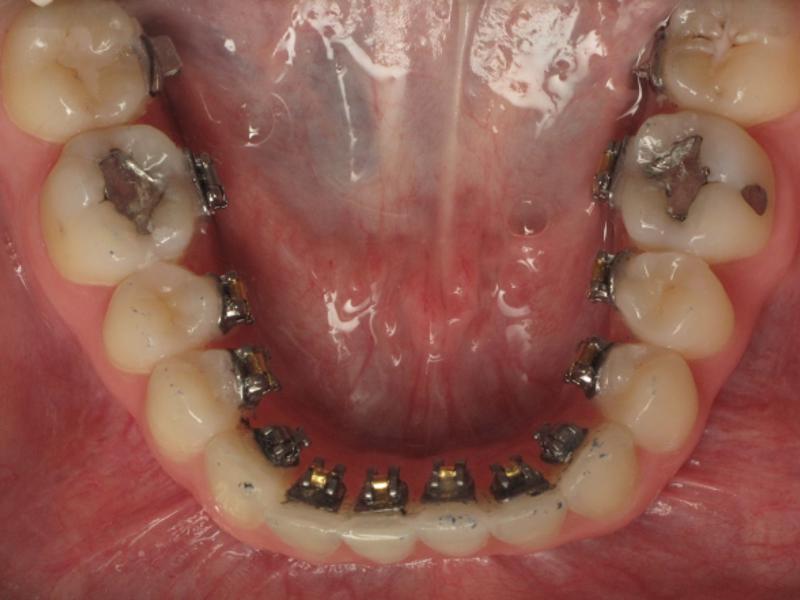

Ortodonti dişlerdeki konum bozukluğunu, çapraşıklığı, ayrıklığı düzelten bir tedavidir. Ortodontik tedaviden sonra dişlerinizde belirgin bir fark olacaktır. Ama düzelen dişleri bozulmadan tutmakta en az ortodonti tedavisi kadar önemlidir. Çünkü ortodonti tedavisi zor bir süreçtir, vakit ayırmanız gerekir, zaman zaman dişlerinizde ağrılar oluşur ve maliyettir. Bu kadar zahmetin altına girip dişlerinizi düzelttirdikten sonra tekrar bozulması canınızı çok sıkacaktır. Ortodonti tedavisinden sonra di